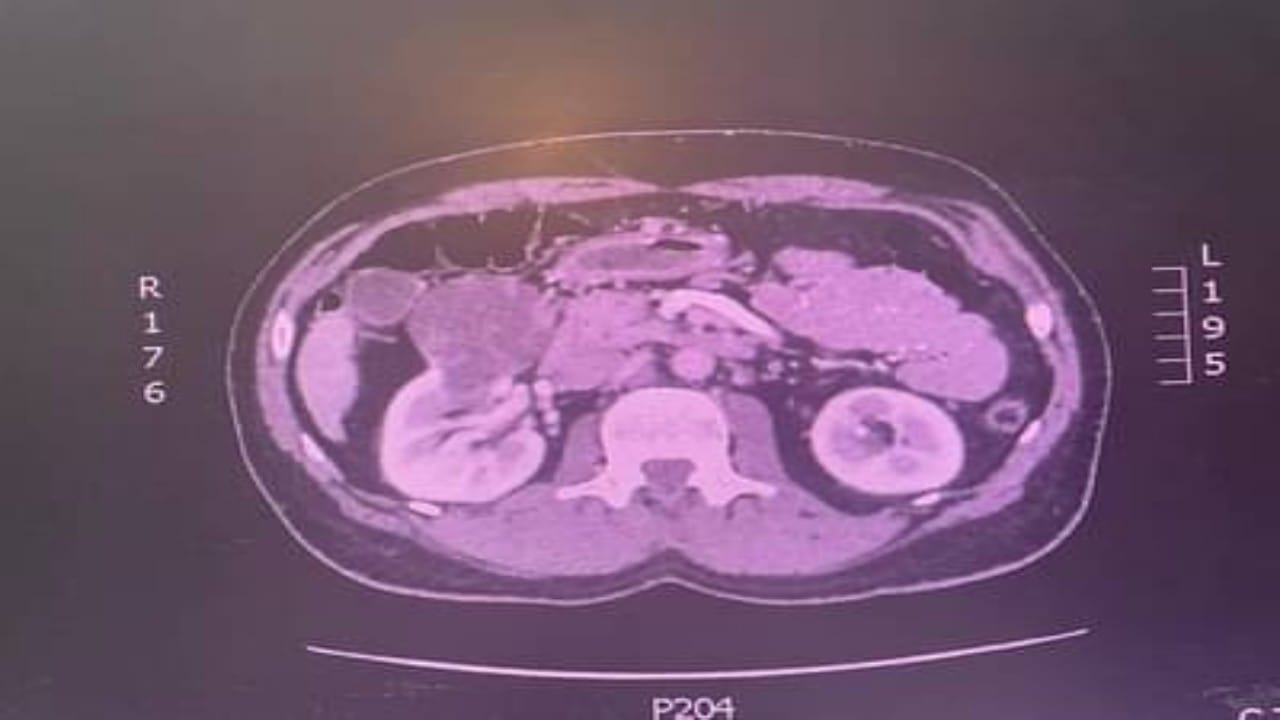

استئصال ورم كلوي لمريض خمسيني في الطائف